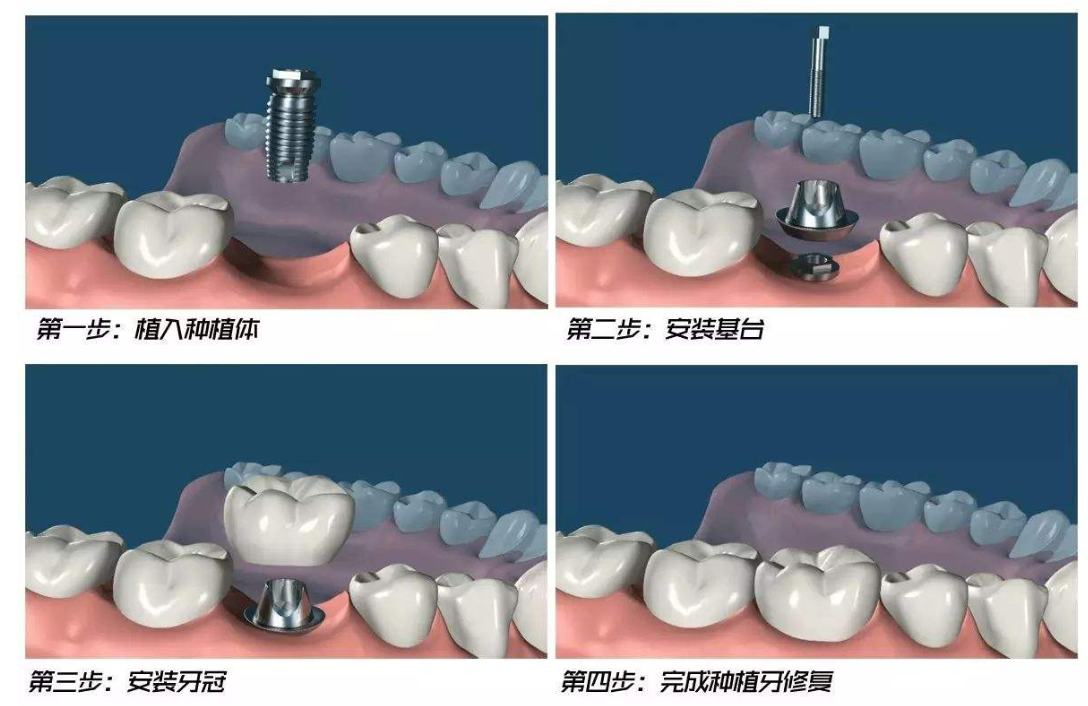

随着种植牙技术的日趋成熟,种牙已成为缺牙患者修复缺失牙的理想选择方式。但是糖尿病患者缺牙后是否可以像普通人一样去做种植牙?是否存在风险?是否有长期的保障?今天,我们一起来了解,糖尿病患者种牙知识。

种植牙成功的关键在于骨结合的愈合效果,当血糖控制良好时,糖尿病患者种植后能够发生骨结合,当血糖控制不良时,骨结合会受到不良影响。

合适的种植体:选择提高愈合周期的种植体,愈合周期可以最短缩短到3-4周。